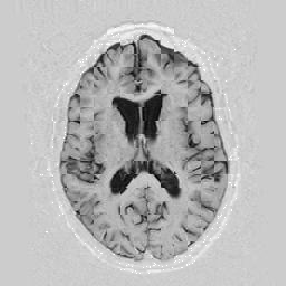

Another larger group of experiments enabled me to study the effects of multi-scale NRR. The results are shown in the form of chequerboard images in Figure [*]. In terms of resolution levels, higher numbers mean that the images are coarser.

Figure: Multi-scale NRR (increasing resolution). From left to right, top then bottom:before NRR; after 5 iterations of NRR at level 2 (higher is coarser); after another 5 iterations of NRR at level 1.